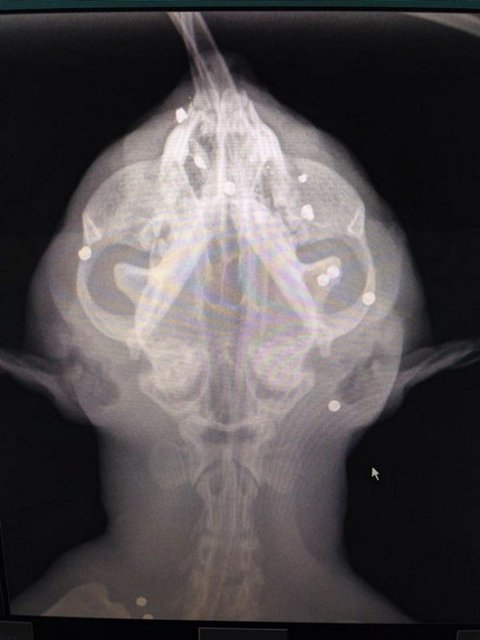

몸에서 40개의 총알이 발견된 고양이

몸에 총을 맞고 발견된 고양이의 몸에서

무려 40개의 파견 조각이 발견돼 누리꾼들이 분노하고 있다

25일(현지시간) 영국 일간 미러에 따르면

영국 잉글랜드 남서부의 콘웰(Cornwall)에서

6살짜리 고양이 한 마리가 샷건(산탄총)에 맞은 채 발견돼 구조됐다고 보도했다

이 고양이는 양쪽 대퇴골과 허리 머리 등 온몸에 총을 맞았고

무려 40개 이상의 파편이 박혔다고 치료를 담당했던 수의사가 설명했다

수의사인 스티브 와이엇(Steve Wyatt)은 여러차례 수술을 마친 뒤

고양이의 몸에서8~9개 유탄을 제거했다